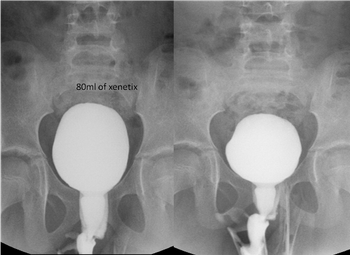

A 7-year-old girl with day and night urge incontinence. Voiding cystourethrogram performed. Low capacity of bladder and patient started voiding after 80ml of contrast injection in urinary bladder through catheter. Unusual dilatation of urethra, giving “spinning top” appearance.